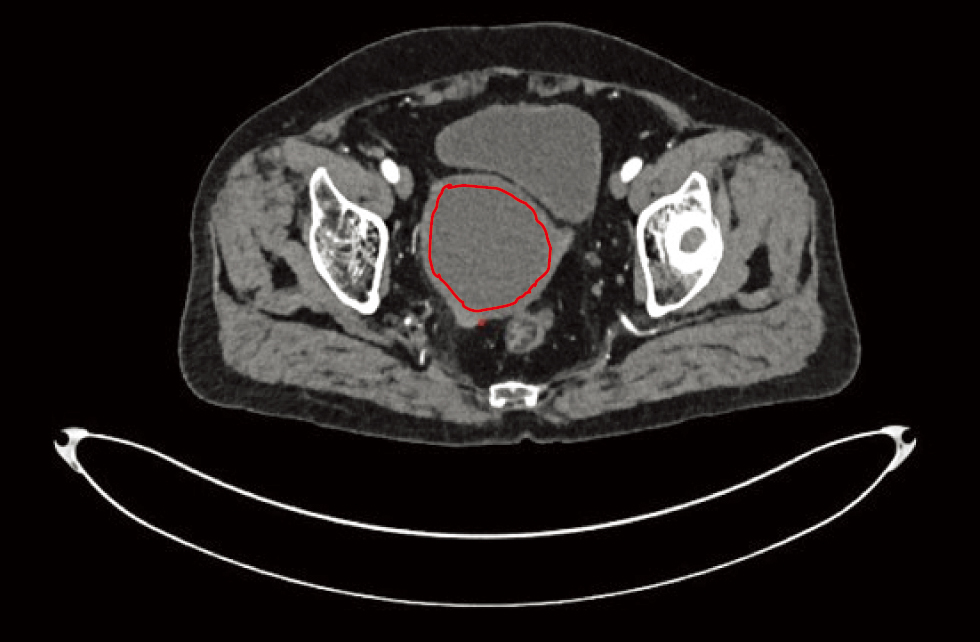

牛勤, 吴小勤. 比较术前CT、MRI检查在浸润性宫颈癌诊断中的应用价值[J]. 现代医用影像学, 2024, 33(7):1282-1285. doi: 10.3969/j.issn.1006-7035.2024.07.027.